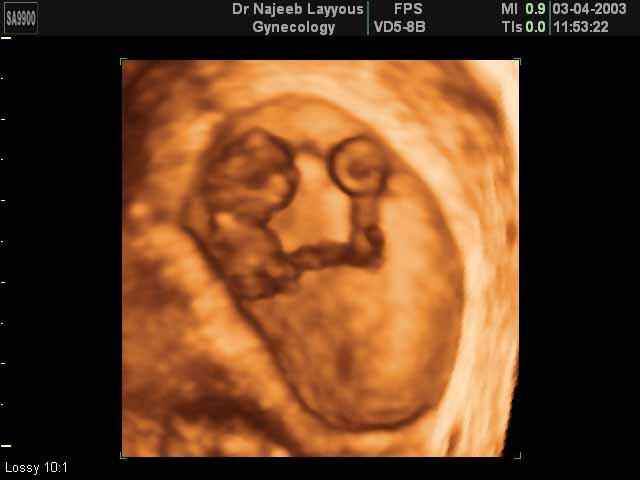

- First Trimester Ultrasound Photos

3D First Trimester Ultrasound Scan Photos ( Early Pregnancy Ultrasound Photos ) | Dr N Layyous